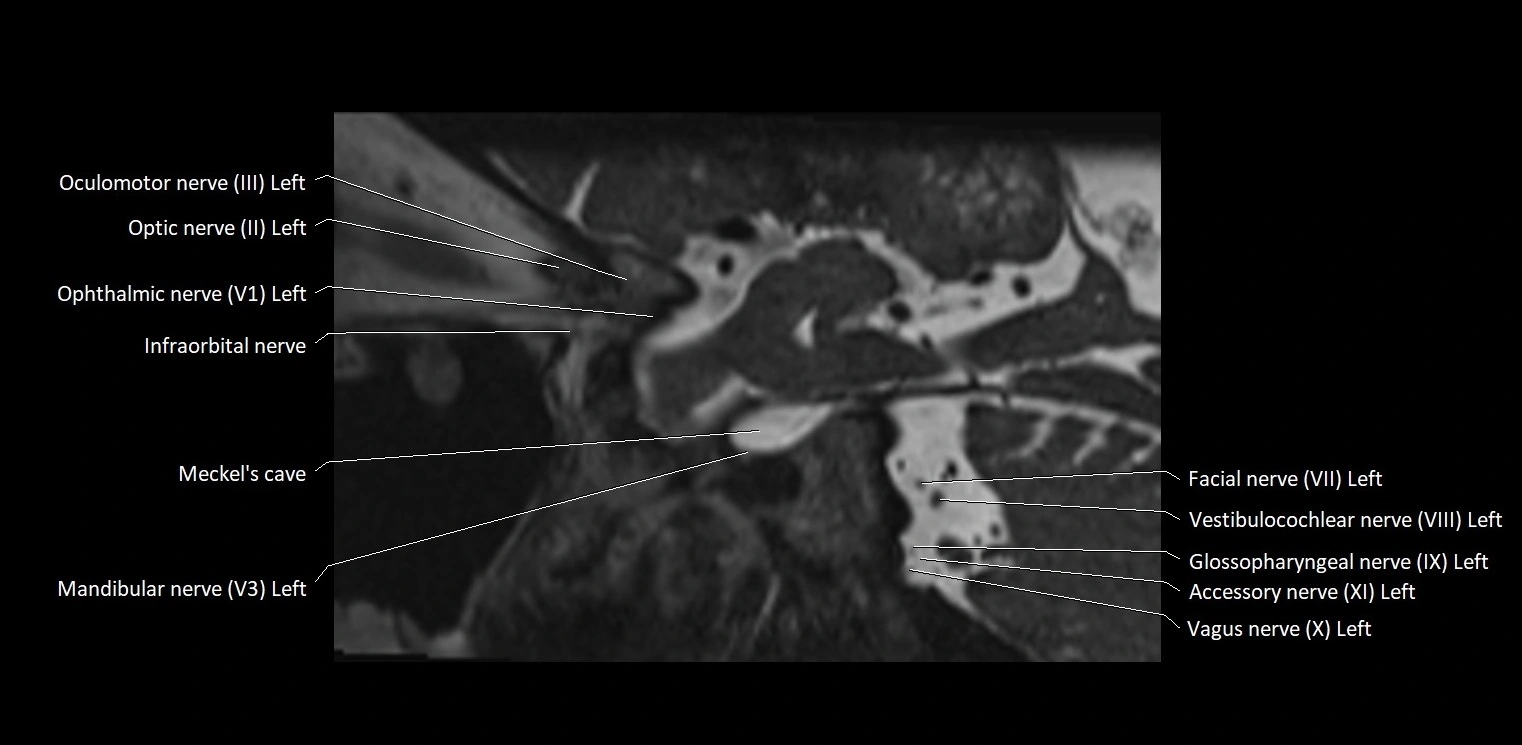

MRI Appearance

• The abducens nerve is a small, thin, linear structure

• Best visualized on high-resolution T2-weighted 3D MRI sequences (e.g., FIESTA or CISS)

• Seen as a hypointense (dark) line running from the brainstem at the pontomedullary junction, traversing the prepontine cistern, and entering Dorello’s canal under the petrosphenoidal ligament, then into the cavernous sinus, and finally the orbit

• May be challenging to visualize in standard MRI due to its small size

• Pathology may be inferred by absence, displacement, or enhancement of the nerve

MRI images

image